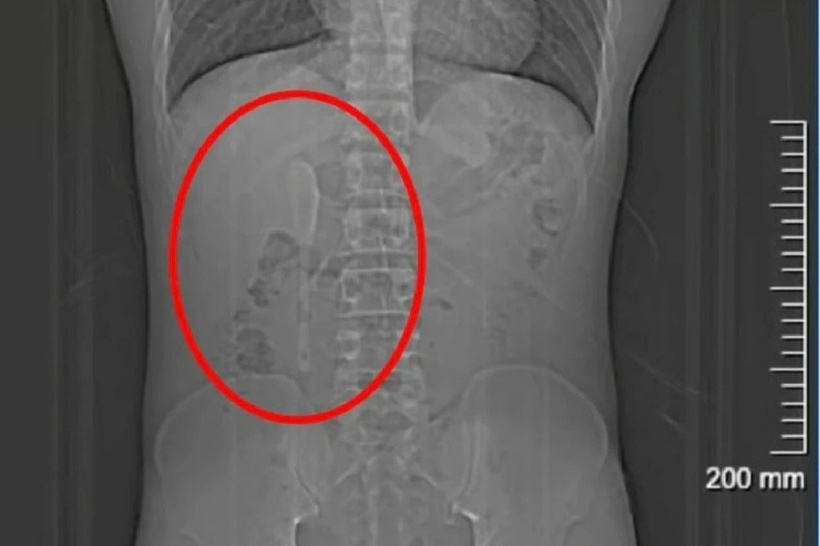

Tuy nhiên, thay vì một miếng nhựa, bác sĩ tại Bệnh viện Trung Sơn (Thượng Hải) đã phát hiện một chiếc thìa sứ dài 15cm bị kẹt trong cơ thể anh.

Giáo sư Chu Bình Hồng, Giám đốc Trung tâm nội soi Bệnh viện Trung Sơn, là người trực tiếp chỉ đạo ca phẫu thuật. Việc lấy chiếc thìa gặp nhiều khó khăn do dị vật có kích thước lớn và vị trí phức tạp: đầu thìa cắm vào bóng tá tràng, trong khi phần tay cầm dài uốn gập và kẹt cứng tại điểm giao giữa phần đi xuống và phần ngang của ruột non. Bề mặt gốm trơn nhẵn cũng khiến các dụng cụ nội soi thông thường không thể giữ chặt.

Chiếc thìa sứ dài 15cm bị kẹt trong cơ thể anh. Ảnh: QQ.